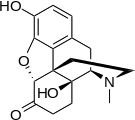

Structures of Morphine family

| Morphine family | ||||

|---|---|---|---|---|

14-Hydroxymorphine 14-Hydroxymorphine |

2,4-Dinitrophenylmorphine 2,4-Dinitrophenylmorphine |

6-Methyldihydromorphine 6-Methyldihydromorphine |

6-Methylenedihydrodesoxymorphine 6-Methylenedihydrodesoxymorphine |

6-Acetyldihydromorphine hydrochloride 6-Acetyldihydromorphine hydrochloride |

Azidomorphine Azidomorphine |

Chlornaltrexamine Chlornaltrexamine |

Chloroxymorphamine Chloroxymorphamine |

Desomorphine Desomorphine (Dihydrodesoxymorphine) |

Dihydromorphine Dihydromorphine |

Ethyldihydromorphine Ethyldihydromorphine |

Hydromorphinol Hydromorphinol |

Methyldesorphine Methyldesorphine |

N-Phenethylnormorphine N-Phenethylnormorphine |

6-nicotinoyldihydromorphine 6-nicotinoyldihydromorphine |

RAM-378 RAM-378 | ||||